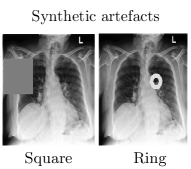

The abilities of Mahalanobis score were studied using CheXpert [13], a multi-label collection of chest X-rays. Subsequent experiments were performed under three settings, summarised in Fig. 2. In the first setting, studied here, we used scans containing either Cardiomegaly or Pneumothorax. We trained a ResNet18 on 90% of these images to classify between the two classes (ID task), and held-out 10% of the data as ID test cases. We generated an OOD test set by adding a synthetic artefact at a random position to these held-out images.

Square artefact: Firstly, grey squares, of sizes 10, 7.5 and 5 % of the image area, were introduced to create the OOD cases. We processed ID and OOD data, measured their after every module in the network and plotted the AUROC score in Fig. 3. We emphasize the following observations. The figure shows that larger square artefacts are easier to detect, with this OOD pattern being easier to detect in earlier layers. Moreover, we observed that AUROC is poor at the last hidden layer (LHL), which is a common layer to apply in the literature [2, 4, 5, 23, 28, 30]. The performance of this sub-optimal configuration may be diverting the communityβs attention, missing the methodβs true potential. The results also show AUROC performance in general improves after a ReLU module, compared to the previous convolution and BN of the corresponding layer. Similar results were found with VGG16 but not shown due to space constraints.

Ring artefact: The experiments were repeated with a white ring as the synthetic artefact, and results were compared with the square artefact (Fig. 4). The figure shows the AUROC for different OOD patterns peak at different depths of the network. The figure shows the layers and optimised linear coefficients for each artefact for (Eq.Β 4), highlighting that the ideal weighting of distances for one OOD pattern can cause a degradation in the performance for another, there is no single weighting that optimally detects both patterns. As the types of OOD patterns that can be encountered are unpredictable, the idea of searching for an optimal weighting of layers may be ill-advised - implying a different application of this method is required.